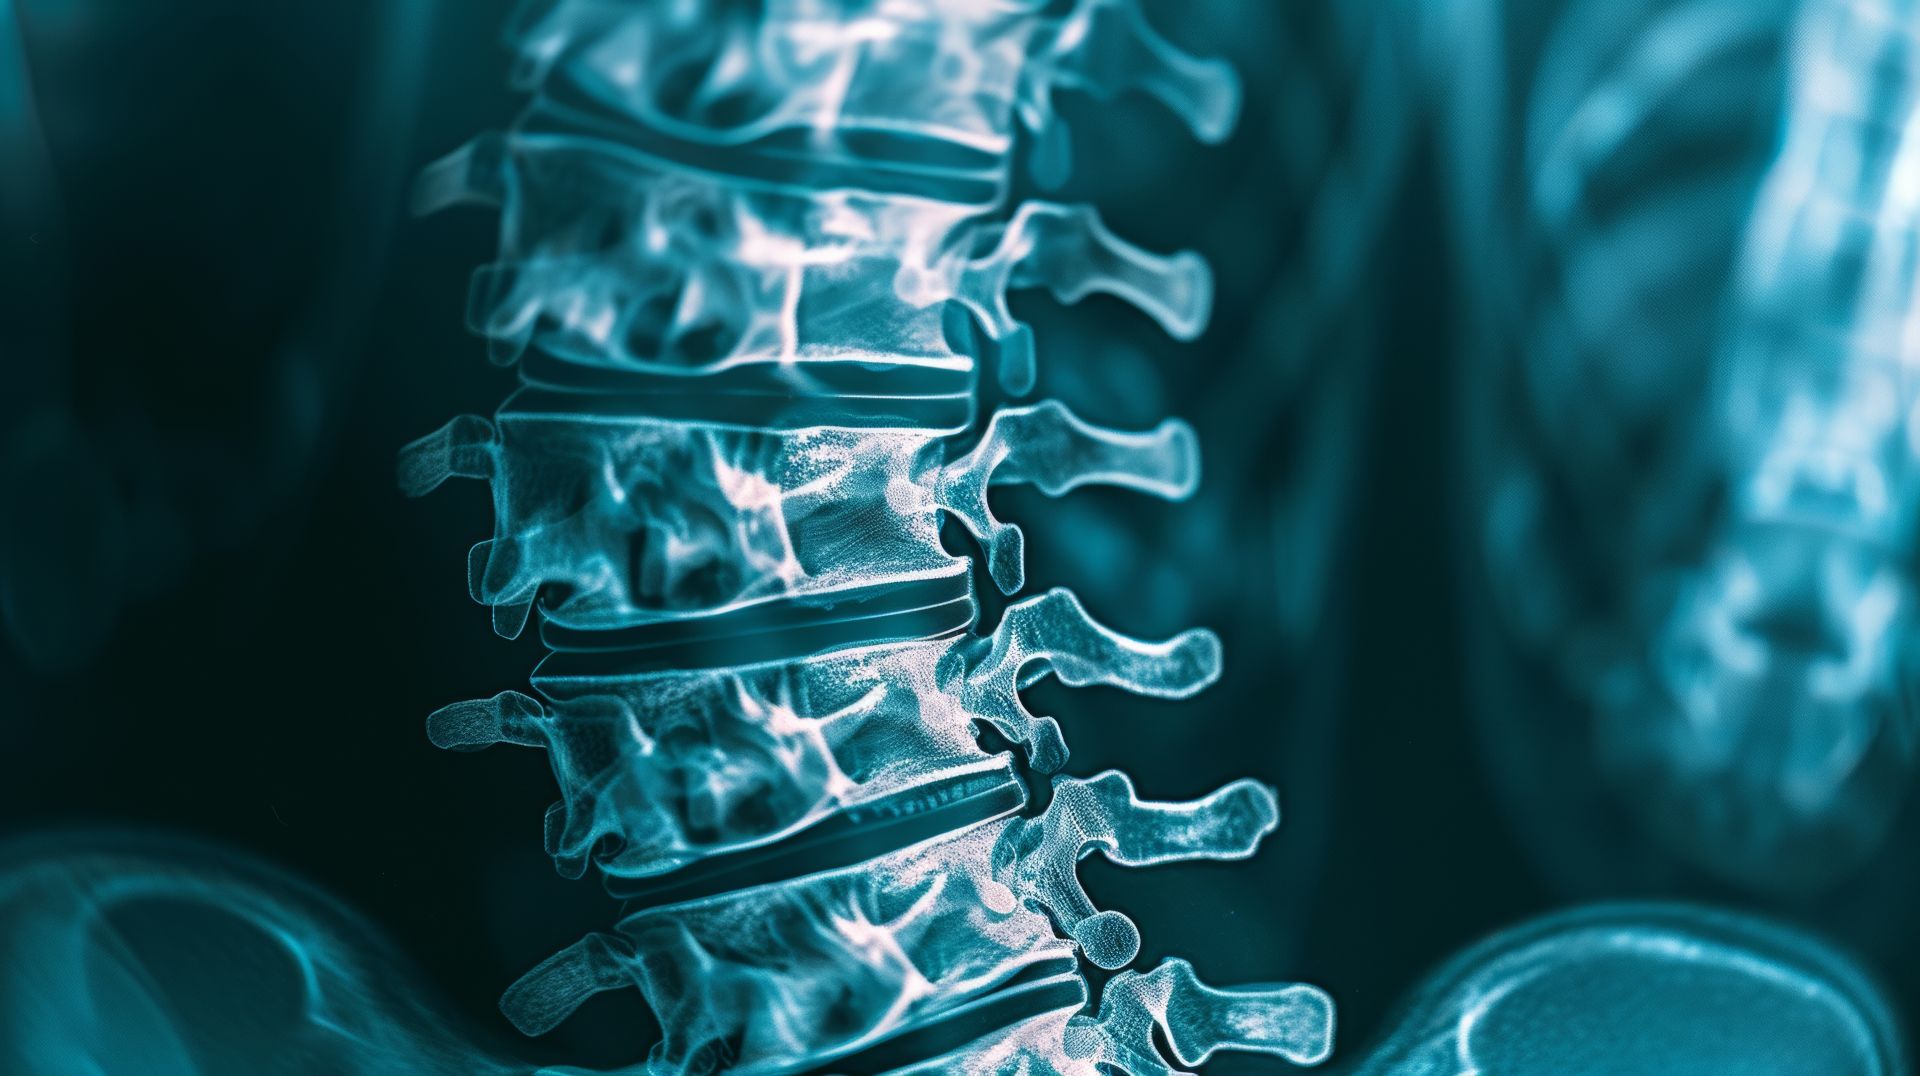

Novadip’s ‘off-the-shelf’ spine fusion product shows early efficacy and safety in studies

Novadip Biosciences has announced encouraging new data for NVDX3, its allogenic bone grafting product derived from adipose tissue-derived stem cells, reporting strong early results in both preclinical and clinical settings.

Early human data appear to support these findings. Interim 12-month results from a phase 1b/2a clinical trial (NVDX3-CLN02, NCT05961956) in five adults undergoing single-level lumbar spine fusion surgery showed no NVDX3-related adverse events and early signs of bone fusion. Patients in the study — aged 57 to 74 and treated using a transforaminal interbody fusion (TLIF) approach — also experienced reductions in pain.

Following an Investigational New Drug (IND) clearance for NVDX3 in November 2024, Novadip is preparing to launch a phase 2b/3 clinical trial for cervical spine fusion in the U.S., with patient recruitment expected to begin in November 2025.